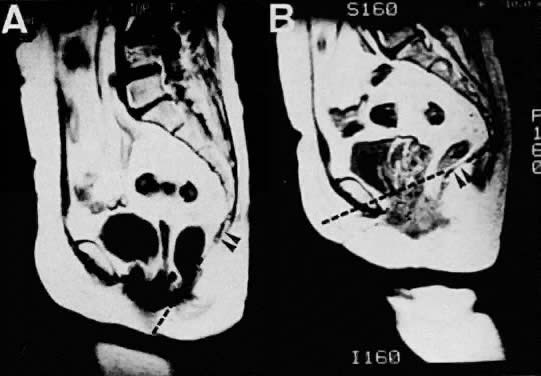

Fig. 15. Sagittal MR images of a 62-year-old patient with uterine prolapse before corrective surgery (A) and after surgery (B). Note that the levator plate is highlighted by the dashed line and does not cross the symphysis prior to surgery but clearly crosses the symphysis after surgery.(Ozasa H, Mori T, Togashi K: Study of uterine prolapse by magnetic resonance imaging: Topographical changes involving the levator ani muscle and the vagina. Gynecol Obstet Invest 34:43, 1992) Volume 1, Chapter 93